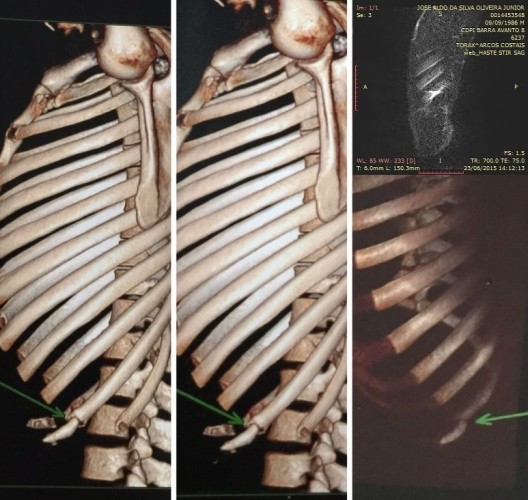

“Unfortunately, I fractured my rib during a training session, which I can prove from an official medical report, and besides trying my best to fight, I was forced the other way and that made me really sad. Only I, my family, coaches and teammates know how hard I worked to represent Brazil again.